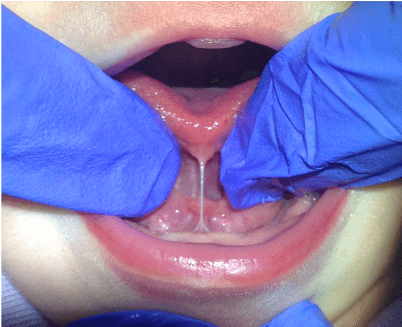

- Labial (lip) frenum: Normal embryonic piece of fibromucous membrane tissue in the midline of the under-surface of the upper lip joining lip to gums

Lesson #3: What is a Lip Tie?

When upper labial frenum is short or inappropriately attached, restricting mobility and function. Kotlow classification system (Classes 1-4) used alongside functional analysis.